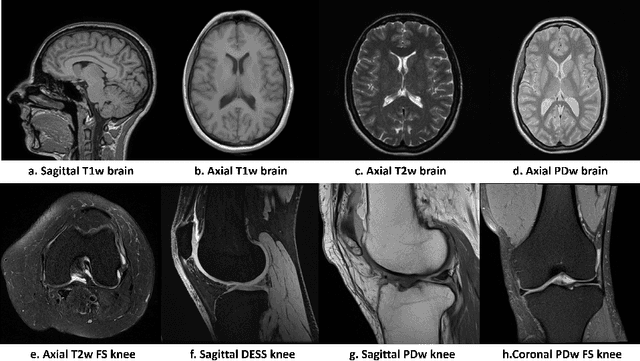

Abstract:Magnetic resonance (MR) images exhibit various contrasts and appearances based on factors such as different acquisition protocols, views, manufacturers, scanning parameters, etc. This generally accessible appearance-related side information affects deep learning-based undersampled magnetic resonance imaging (MRI) reconstruction frameworks, but has been overlooked in the majority of current works. In this paper, we investigate the use of such side information as normalisation parameters in a convolutional neural network (CNN) to improve undersampled MRI reconstruction. Specifically, a Side Information-Guided Normalisation (SIGN) module, containing only few layers, is proposed to efficiently encode the side information and output the normalisation parameters. We examine the effectiveness of such a module on two popular reconstruction architectures, D5C5 and OUCR. The experimental results on both brain and knee images under various acceleration rates demonstrate that the proposed method improves on its corresponding baseline architectures with a significant margin.

Abstract:Deep neural networks have been extensively studied for undersampled MRI reconstruction. While achieving state-of-the-art performance, they are trained and deployed specifically for one anatomy with limited generalization ability to another anatomy. Rather than building multiple models, a universal model that reconstructs images across different anatomies is highly desirable for efficient deployment and better generalization. Simply mixing images from multiple anatomies for training a single network does not lead to an ideal universal model due to the statistical shift among datasets of various anatomies, the need to retrain from scratch on all datasets with the addition of a new dataset, and the difficulty in dealing with imbalanced sampling when the new dataset is further of a smaller size. In this paper, for the first time, we propose a framework to learn a universal deep neural network for undersampled MRI reconstruction. Specifically, anatomy-specific instance normalization is proposed to compensate for statistical shift and allow easy generalization to new datasets. Moreover, the universal model is trained by distilling knowledge from available independent models to further exploit representations across anatomies. Experimental results show the proposed universal model can reconstruct both brain and knee images with high image quality. Also, it is easy to adapt the trained model to new datasets of smaller size, i.e., abdomen, cardiac and prostate, with little effort and superior performance.